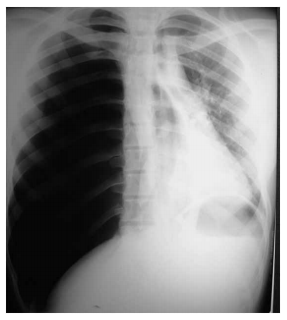

Paciente portador de asma brônquica é trazido por familiares ao pronto atendimento com queixa de dispneia súbita, dor torácica em hemitórax direito e dificuldade para falar. O exame físico revela o paciente sonolento, torporoso, taquidispneico e com cianose de extremidades. Escala de Glasgow na chegada = 8 (abertura ocular = 2, resposta verbal = 2, resposta motora = 4), PA = 100 x 60 mmHg, FC = 120 bpm e SpO2 = 73%. Realizada radiografia de tórax na sala de emergência (ilustrada a seguir).

Assinale a alternativa que contém a melhor estratégia terapêutica inicial.